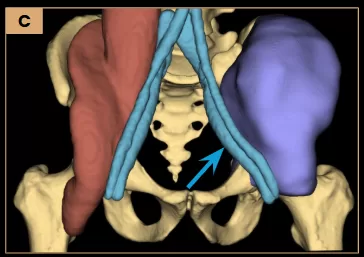

Left internal hemipelvectomy was performed with curative intent.

Image C: Schematic illustration for 3D model printing, highlighting the tumor in purple and its close proximity to the external iliac vessels (arrow).

Surgery

Images A and B: Left internal hemipelvectomy with reconstruction using surgical mesh (arrow – white). Intraoperative video (C) highlights the close anatomical proximity of the tumor to the external iliac vessels (arrow – blue).